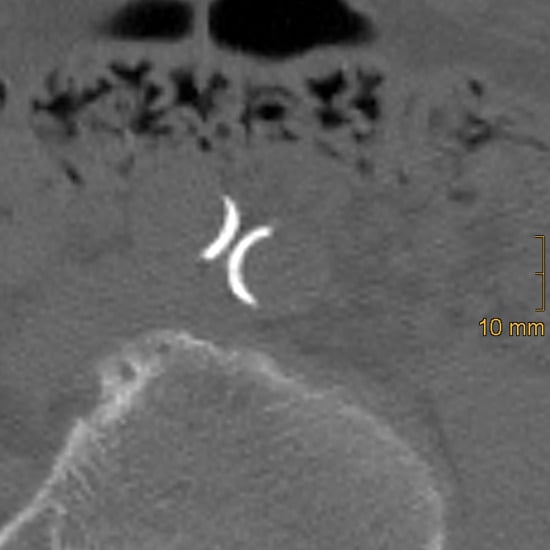

2.2. Assessment of Vascular Calcification

2.2.2. Iliac Artery Calcification